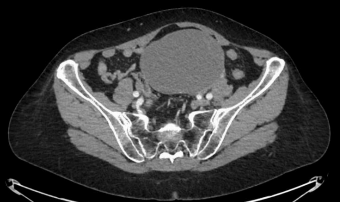

SolicitanTAC abdominal que evidencia gran masa pélvica de origen anexial izquierdo, de unos 12 centímetros, de predominio quístico, compatible con tumor ovárico epitelial (tumor borderline o adenocarcinoma mucinoso/seroso). Sin evidencia de diseminación adenopática o a distancia).